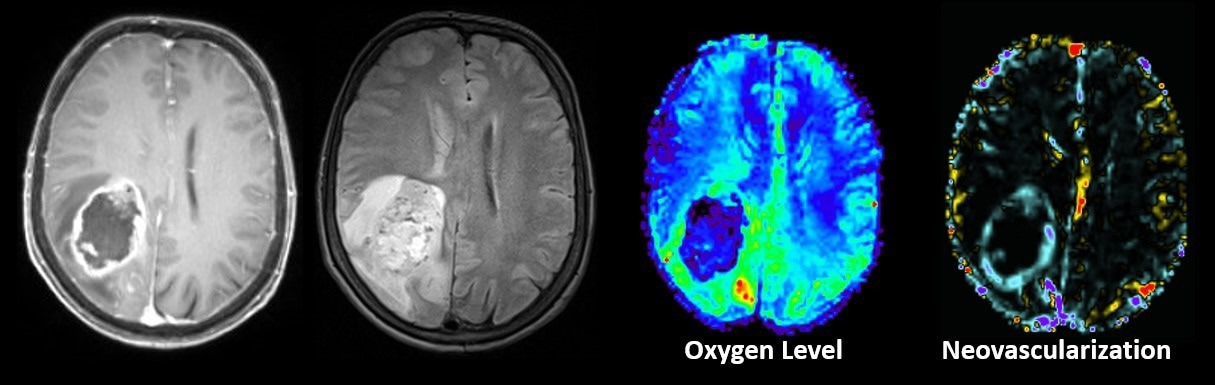

Image Credit: © UK St. Pölten/Stadlbauer

Stadlbauer, A., et al. (2024). Machine Learning-Based Prediction of Glioma IDH Gene Mutation Status Using Physio-Metabolic MRI of Oxygen Metabolism and Neovascularization (A Bicenter Study). Cancers. doi.org/10.3390/cancers16061102.